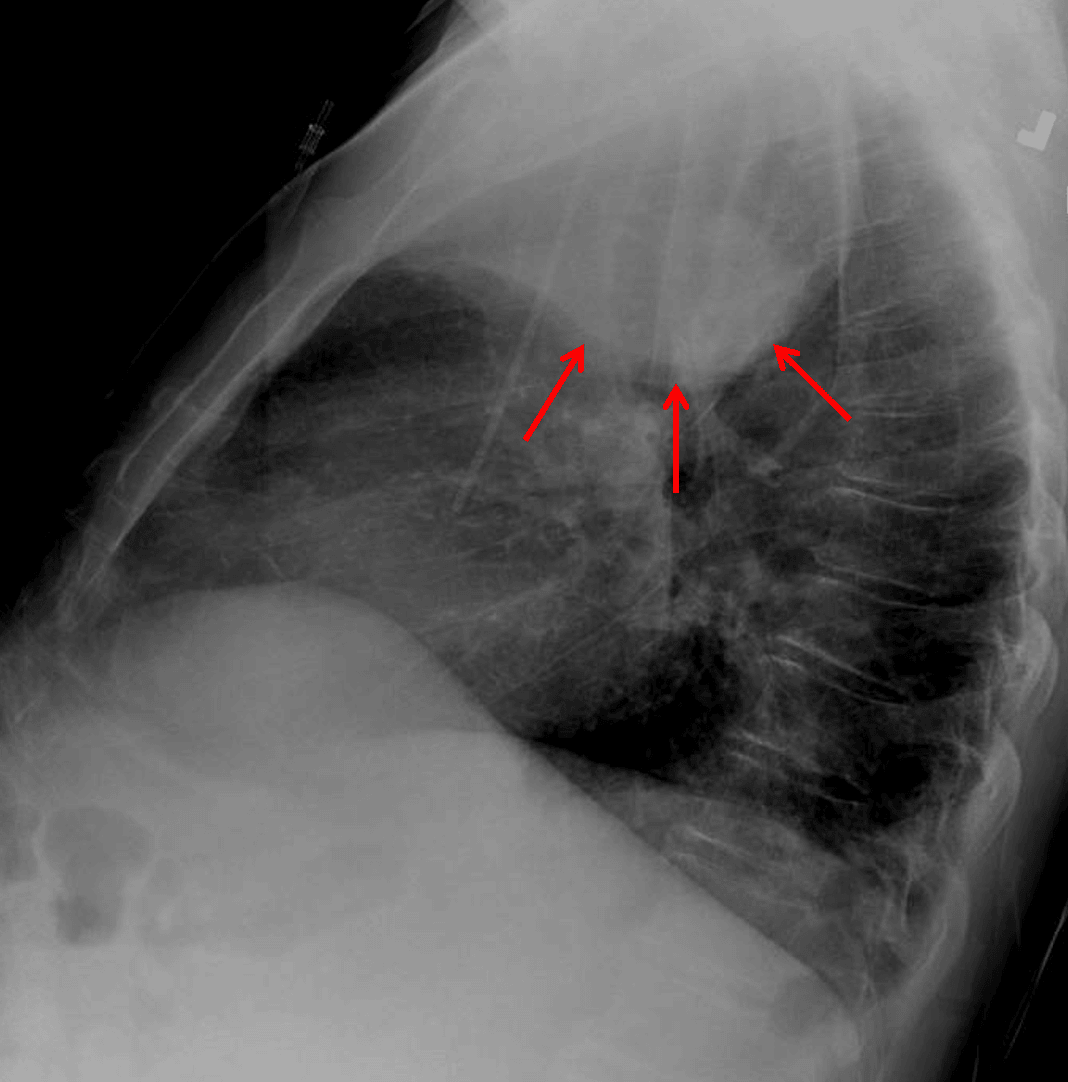

Right upper lobe collapse. Lateral view shows a paradoxical bulging appearance along the inferior margin of the collapsed lobe concerning for mass (red arrows).